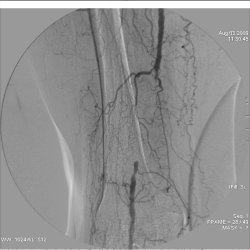

На обычных рентгенограммах не видны артерии, вены и лимфатические сосуды. Для того чтобы сосуды можно было увидеть, применяются методы ангиографии.

Ангиография позволяет выявить повреждения и пороки развития сосудов (аневризмы, сужения сосудов, мальформации), нарушения проходимости сосудов, повреждения и пороки развития различных органов, опухоли и т.д.

Через прокол в бедренной артерии в сонную проводится катетер и затем контрастное вещество, видимое под рентгеном (см.рис.)